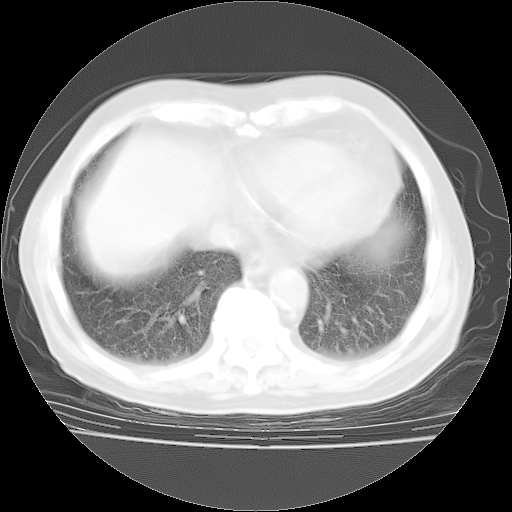

4月28日肺部CT——再次出现类似去年5月9日——磨玻璃样、间有“粟粒样”改变。